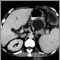

Liver cirrhosis, CT scan